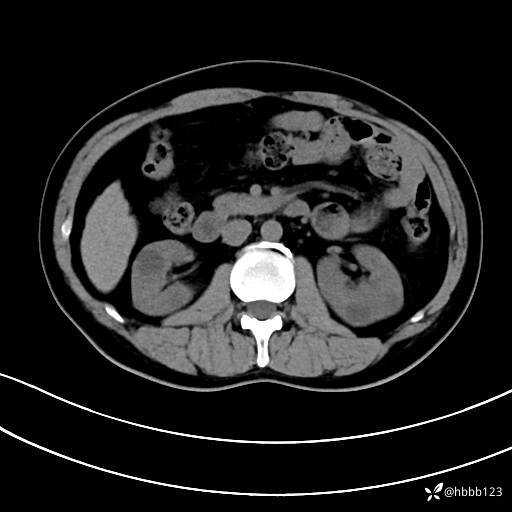

动脉期: